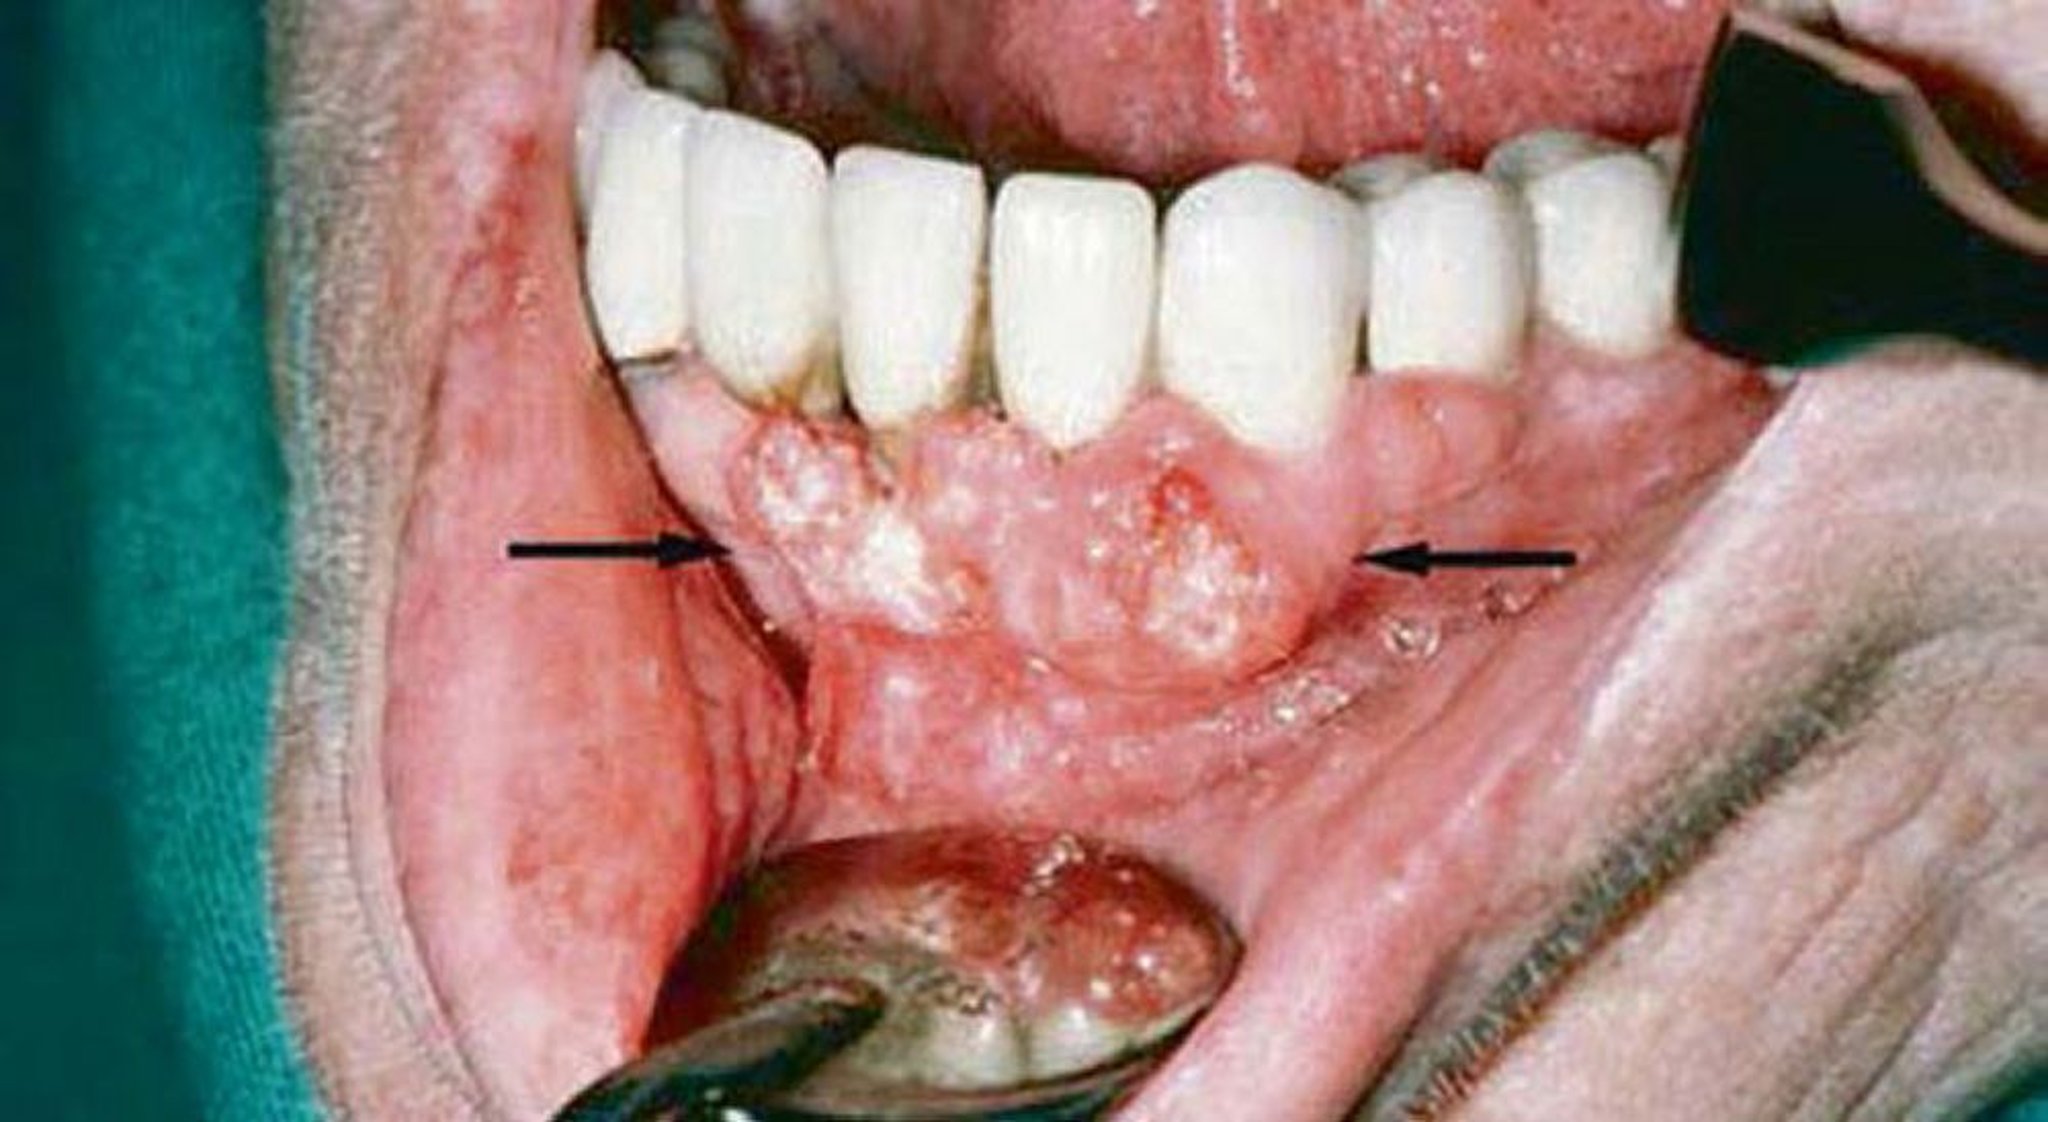

Плоскоклеточная карцинома (поражения десен)

В ходе исследования десны этого пациента была выявлена плоскоклеточная карцинома. Визуализирующие исследования показали прорастание в нижнюю челюсть.